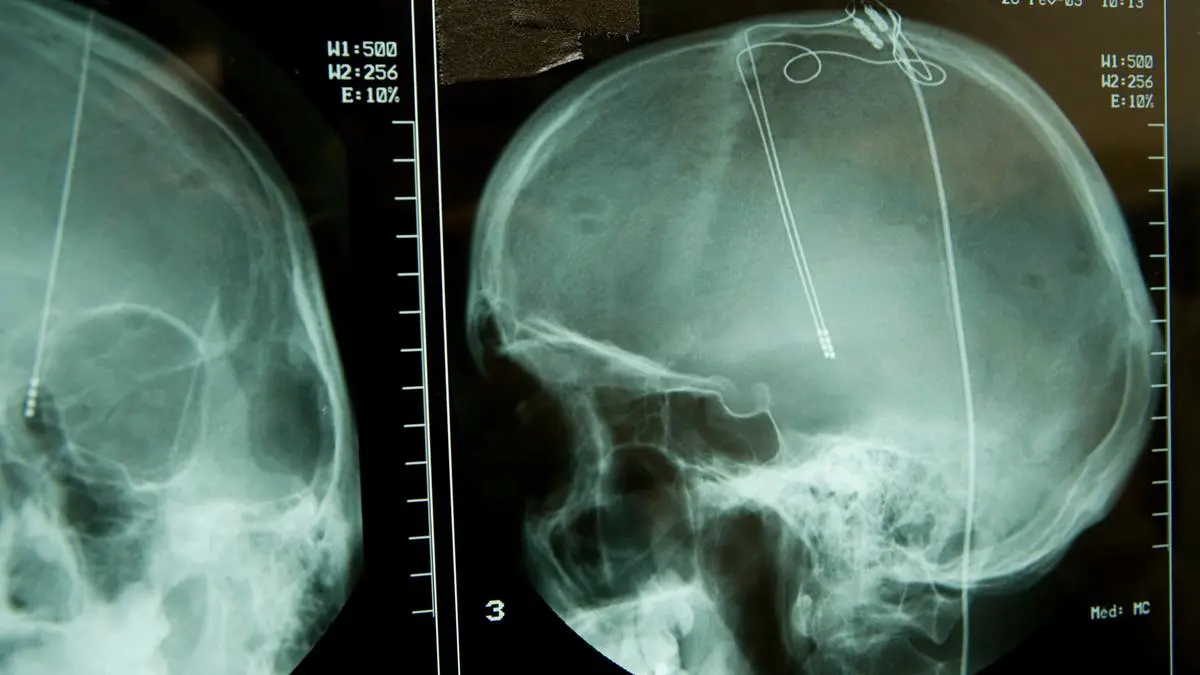

Die Deep Brain Stimulation (DBS) ist eine etablierte neurochirurgische Technik, bei der Elektroden in bestimmte Regionen des Gehirns implantiert werden. (Sujetbild)